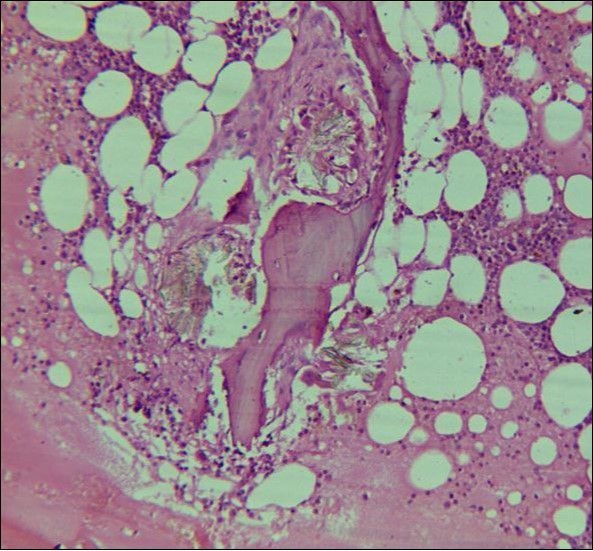

A 24 years old male, presented with the complaints of multiple recurrent renal stones bilaterally. He was on dialysis since last 6 months. His brother had died with chronic renal insufficiency secondary to nephrolithiasis. His routine investigations at the time bone marrow studies revealed anemia with a Haemoglobin of 6.6g/dl, White blood cell count of 5.3 x 109/l; Platelet count of 228 x 109/l. Serum Creatinine was very high 13.9mg/dl. X Ray Abdomen revealed multiple bilateral renal calculi and in addition gall bladder calculi. On ultrasound abdomen his right kidney was 10.5cm x 5.6 cm, had a cyst in the upper pole, multiple calculi were causing hydronephrosis. Left kidney was 8.5cm x 4.8 cm, with multiple calculi. Both kidneys showed increased echogenecity. Serum oxalate levels were 91.2 mg/dl (Normal Range 1-2.4 mg/dl). His Parathyroid MIBI scan was normal, but plasma Parathyroid hormone levels were 373 pg/ml (Normal Range 16 – 87pg/ml). Normochromic normocytic anaemia was present, with normal WBC and platelet count. The bone marrow aspirate was unsuccessful. The trephine biopsy revealed reduced cellularity, depressed erythropoeisis with partly replaced haemopoietic tissue with calcium oxalate crystals (Figure 4) which showed birefringence on polarized light (Figure 5).

Figure 4.Photomicrograph of bone marrow core from case2 showing Para trabecular arrangement of calcium oxalate crystals. Increased fat spaces and depressed erythropoiesis is evident.

Systemic oxalosis can be a primary or a secondary disease. Primary hyperoxaluria Type 1 (PH 1) is due to the deficiency of glyoxylate aminotransferase and Type II due to that of glyoxylate reductase/D-glycerate dehydrogenase. PH 1 is an autosomal recessive disorder characterized by hyperoxaluria, calcium oxalate urinary lithiasis in childhood, nephrocalcinosis and renal failure which in turn leads to high blood oxalate levels and precipitation occurs throughout the body in the skin, blood vessels and joints. Secondary oxalosis occurs due to oxalate-rich diet, increased absorption or production of oxalate and reduced excretion as seen in renal failure. Variable degree of cytopenias or pancytopenia may accompany extensive oxalosis. Bone marrow aspirate may be unsuccessful due to extensive crystal deposition or accompanying fibrosis. Calcium oxalate crystals are well demonstrated on trephine biopsy with associated fibrosis and occasionally granulomas. They have a grey-yellow radial arrangement on hematoxylin and eosin staining and are birefringent under polarized light.4 Liver biopsy is the confirmatory test which demonstrate reduced glyoxylate aminotransferase activity (PH1). Molecular diagnosis, being non-invasive, is preferred, if available.5 An early diagnosis of oxalosis is of immense value, because at a stage when renal failure has not set in, proper management can arrest or at least delay the progress of disease. However, in patients who have already developed renal failure at the time of diagnosis, a combined liver and kidney transplantation offers the only salvation.6